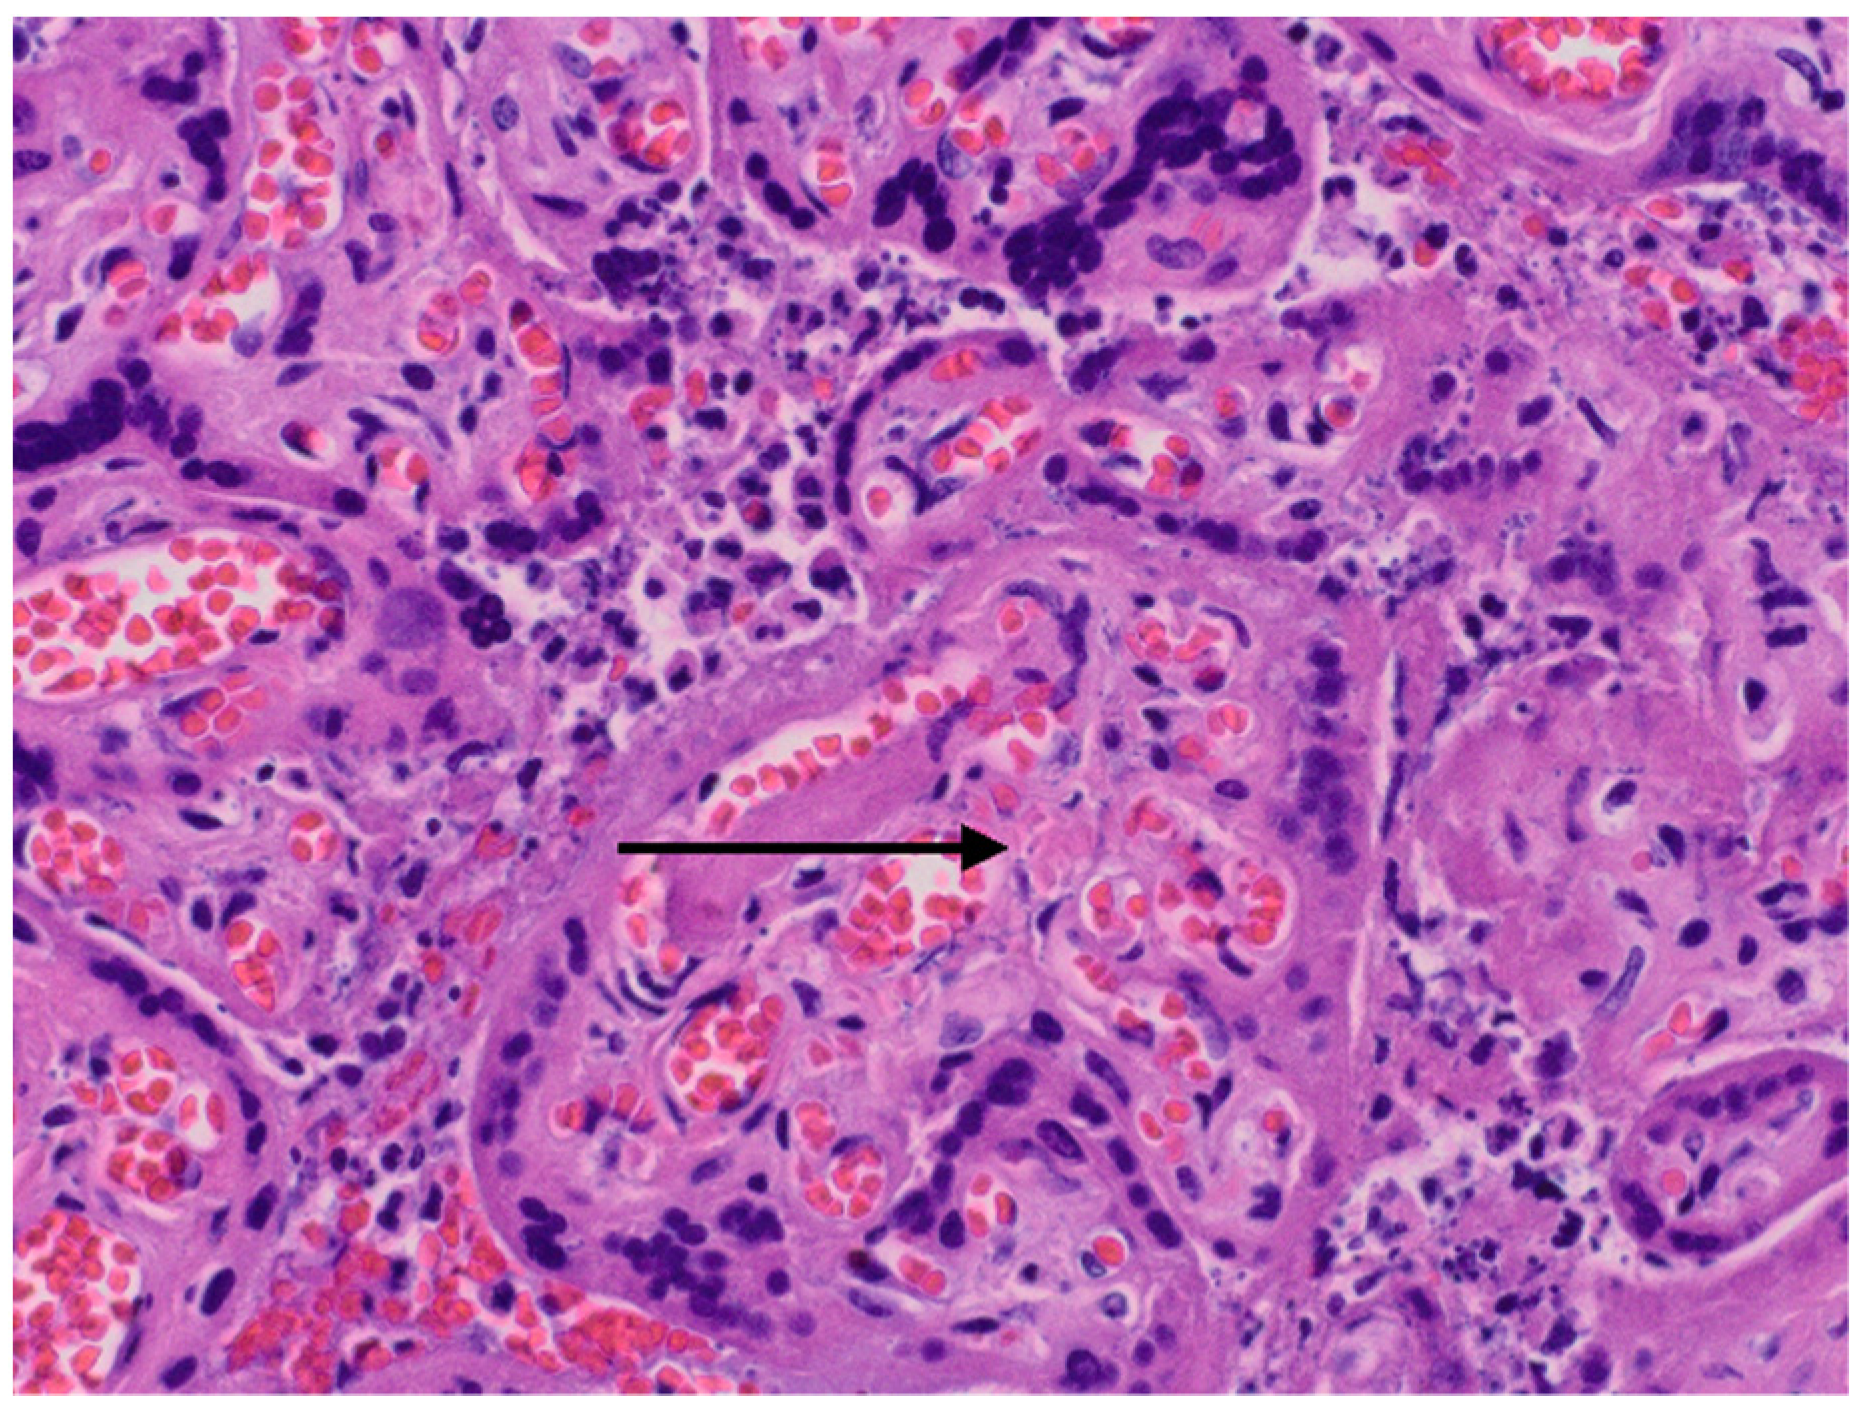

The results of neonatal examinations are summarised in Table 2. Significant changes of D-dimers, fibrinogen, AST were observed. Arterial blood gas test showed: pH 6.618 N: 7.35–7.45), pO2 64.9 mmHg (N: 50–70), pCO2 71.8 mmHg (N: 45–55), cLac-30 mmol/L (N: <2). The results indicated a significant metabolic acidosis, chronic hypoxia and coagulation disorders. Brain ultrasound revealed increased diffuse echogenicity of brain tissue, scanty, high-resistance blood flow. Abdominal ultrasound showed abnormal renal and visceral blood flow. At the same time, anuria, hypoglycaemia and hypotension persisted. The newborn did not respond to the treatment and succumbed 24 h after birth. In the postmortem examination congestion of the entire brain, especially the choroid plexus, the central area around the ventricles, and the meninges was found. The image suggested blockage of the venous outflow. Early, diffuse ischaemic changes with the necrosis in the cerebral cortex, as well as blood clots in small vessels in the brain were visualised. The newborn’s lungs were also congested, with foci of atelectasis. The postpartum histopathology examination revealed a strongly hyperaemic placenta with small infarcts and abundant fibrin deposits (chronic intervillositis) (Figure 2 and Figure 3).

Figure 2.

Histopatological images. Arrow—small infarcts.

The severe course of SARS-CoV-2 infection in pregnancy increases the prothrombotic potential also in the foetal part of the placenta. Postpartum histopathology tests showed the presence of infarction foci and inflammatory infiltrates. Recently, a meta-analysis was published comparing the histopathology examinations of the placenta of pregnant patients with high-risk pregnancy and the placenta of patients with pregnancy complicated by COVID-19 infection. The meta-analysis showed a significant reduction in vascular perfusion, foci of acute and chronic inflammation, foci of thrombosis, areas of fibrin deposits [26,27]. This means that the risk of stillbirth by the COVID positive patient is much higher than in the general population. Similar changes were described in the histopathology examination of the placenta of the presented patients.